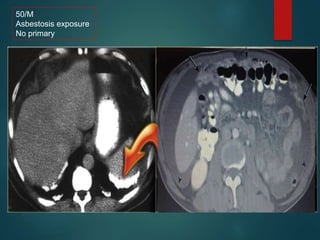

Malignant mesothelioma…

• Sheet like peritoneal thickening.

• Absence of lymphadenopathy

• Ascities is minimal

50/M

Asbestosis exposure

No primary

Malignant mesothelioma… • Justlike pleural mesothelioma ,it is associated with asbestosis exposure • Sheet like peritoneal thickening. • Absence of lymphadenopathy • Ascities is minimal

• #49 Notice the sheet like peritoneal thickening. The diagnosis was suggested because of pleural calcification..